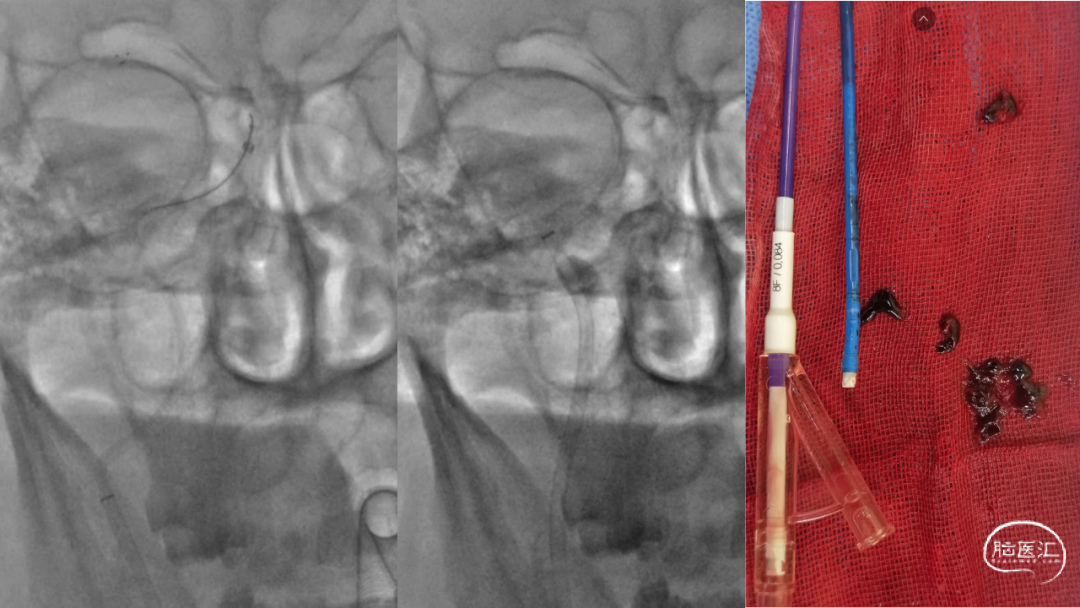

取之有道·第54期|李子付:Flowgate2取栓应用

看李子付解“取之有道”

滑动浏览更多内容